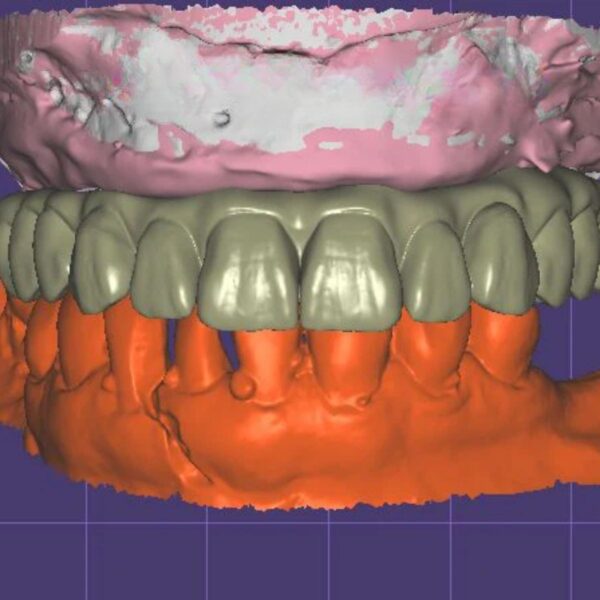

China Dental Design Complex Case Gallery

Challenging Projects That Showcase Our China Dental Design Expertise

Dental Crown Design

Implant Crown Design

Dental Model and Denture Design